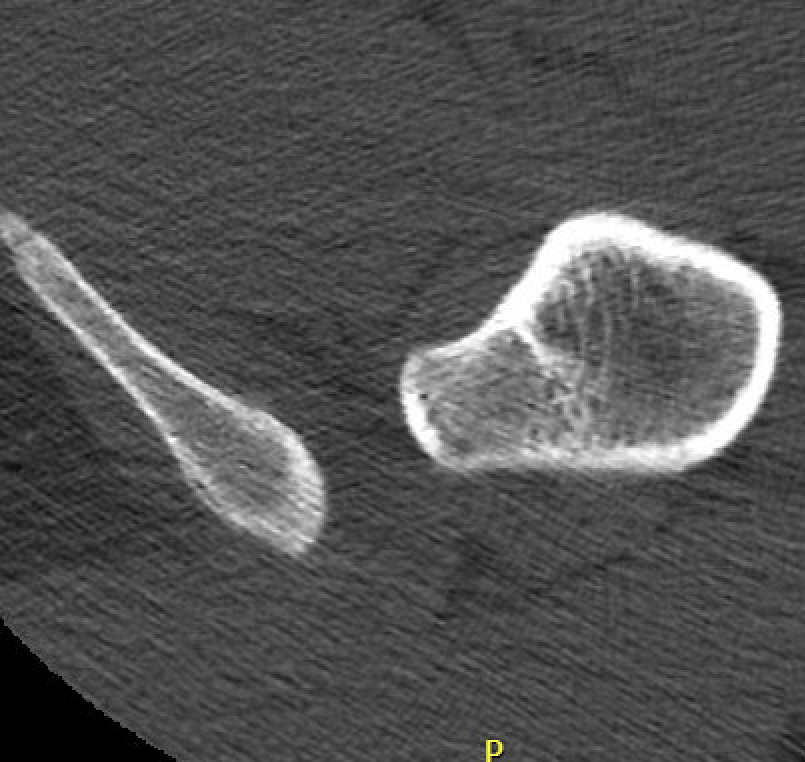

Primary

- enlarged lesser trochanters

- increased proximal femoral anteversion

- coxa valga

CT

IFI

IFIIFIIFI